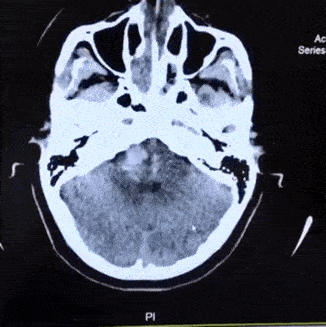

第二次CT复查出血量增加 【右】

保守治疗2天后,病情加重,瞳孔进一步扩大,出血量增加

出血部位波及到桥脑、延髓,量约有5ml,生命体征开始出现不稳定